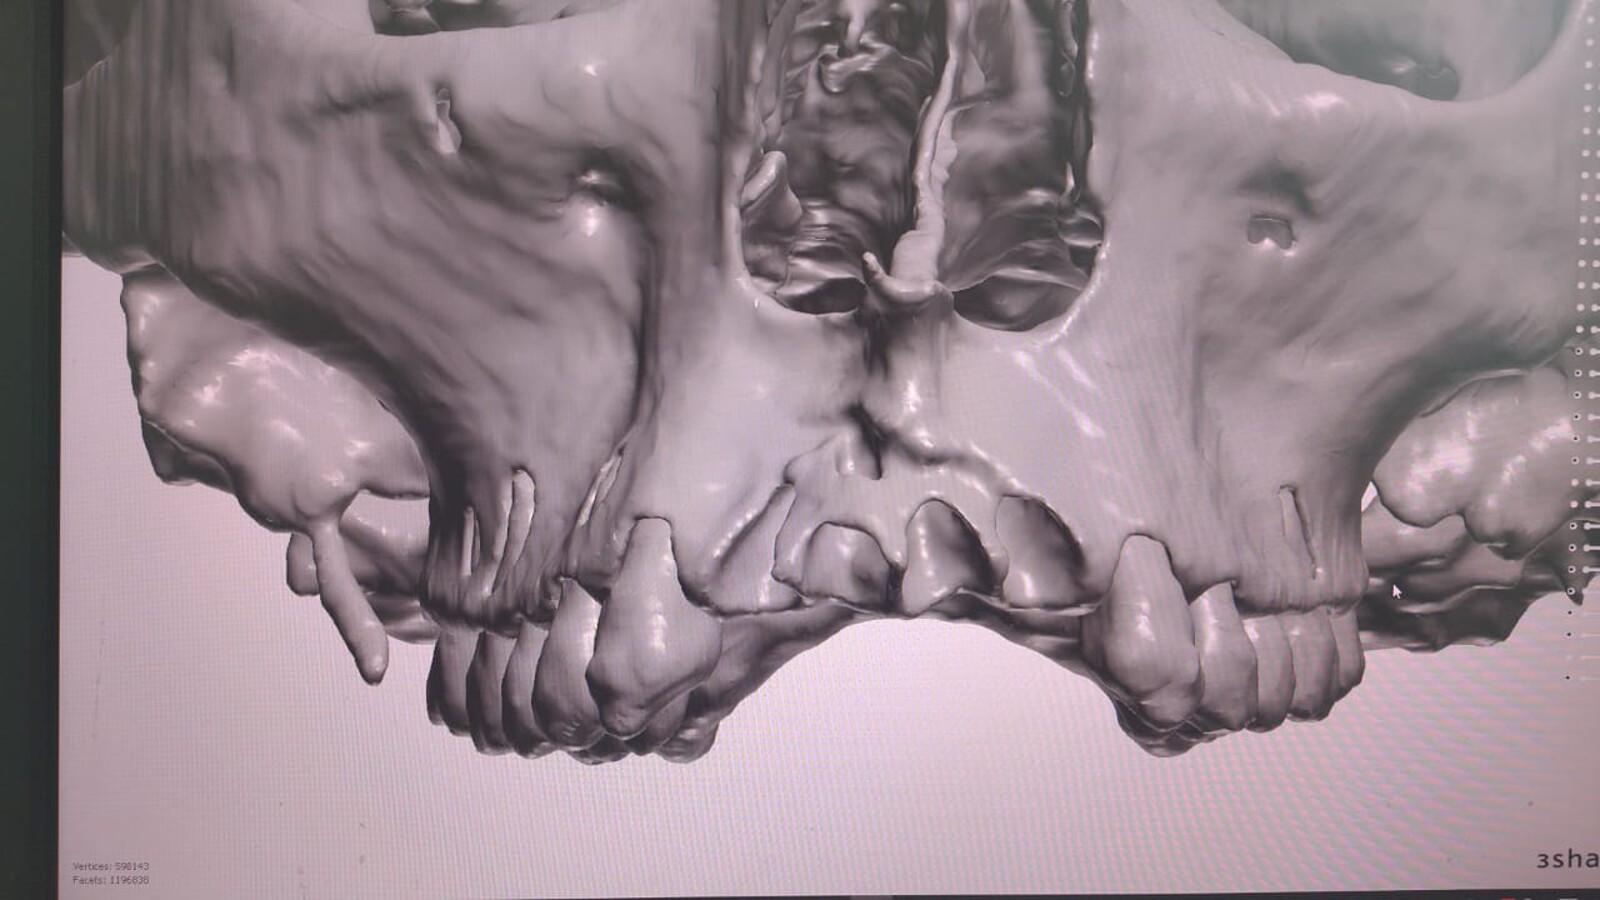

Reconstrucción de una tomografía del maxilar superior.